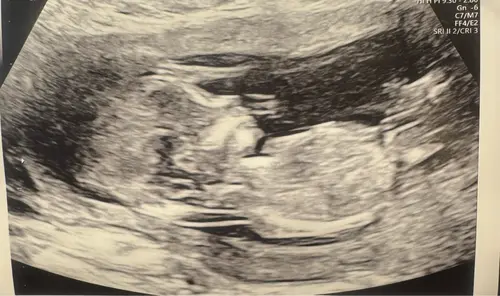

Iemand een idee? In de vorige topic 2x meisje 1x een jongentje werd er gezegd maar vandaag een nieuwe echo gehad bij de 13.4 weken vandaar nogmaals de vraag 😊

Reactie op Wensmoeder0546

Iemand een idee? In de vorige topic 2x meisje 1x een jongentje werd er geze ...

Geen nub te zien